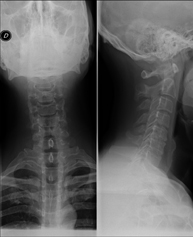

Técnica mediante la cual, utilizando rayos X, se obtienen imágenes del cavum para su estudio. Indicaciones: dificultad respiratoria, anginas de repetición en lactantes y niños. - RX Columna cervical

Técnica mediante la cual, utilizando rayos X, se obtienen imágenes de la columna cervical para su estudio. Indicaciones: traumatismo, contractura cervical, dolor articular. - RX Huesos propios nasales

- RX Columna cervical

Técnica mediante la cual, utilizando rayos X, se obtienen imágenes de la columna cervical para su estudio. Indicaciones: traumatismo, dolor cervical. - RX Columna dorsal